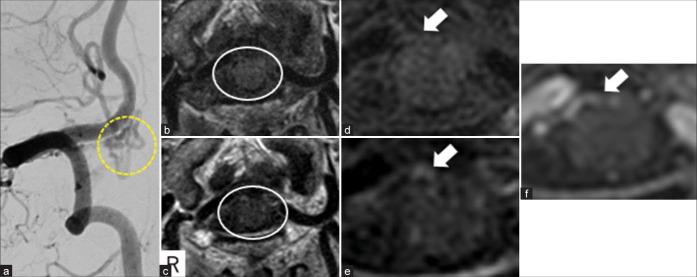

A 70-year-old man presented with a sudden onset of headache. He had Glasgow Coma Scale E4V5M6, world federation of neurosurgical societies (WFNS) Grade I. Fisher group 3 subarachnoid hemorrhage and hydrocephalus were found on head computed tomography. Cerebral angiography showed a spinal AVF at the C1 level of the cervical spine. Magnetic resonance image-enhanced motion sensitized driven equilibrium (MSDE-method showed an enhancing effect in part of the AVF draining vein, but the vascular architecture of this lesion was indeterminate. We performed continuous ventricular drainage for acute hydrocephalus and antihypertensive treatment. Cerebral angiography was performed 30days after the onset of the disease, and was revealed an aneurysmal structure in a portion of the AVF draining vein, which VW-MRI initially enhanced. On the 38 day after onset, he underwent direct surgery to occlude the AV fistula and dissect the aneurysmal structure. Histopathology showed that the aneurysmal structure was varices with lymphocytic infiltration, and hemosiderin deposition was observed near the varices.

一名70岁男性突发头痛。他的格拉斯哥昏迷量表评分为E4V5M6,世界神经外科联合会(WFNS)分级为I级。头部计算机断层扫描发现Fisher 3级蛛网膜下腔出血和脑积水。脑血管造影显示颈椎C1水平有一个脊髓AVF。磁共振成像增强运动敏感驱动平衡(MSDE)方法显示部分AVF引流静脉有强化效应,但该病变的血管结构不明确。我们对急性脑积水进行了持续脑室引流和降压治疗。发病30天后进行了脑血管造影,发现AVF引流静脉的一部分有动脉瘤样结构,VW-MRI最初显示该结构有强化。发病38天后,他接受了直接手术,以闭塞AV瘘并切除动脉瘤样结构。组织病理学显示动脉瘤样结构为伴有淋巴细胞浸润的静脉曲张,在静脉曲张附近观察到含铁血黄素沉积。